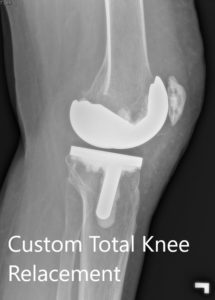

Postoperative X-ray showing the lateral view of the right and the left knee respectively.